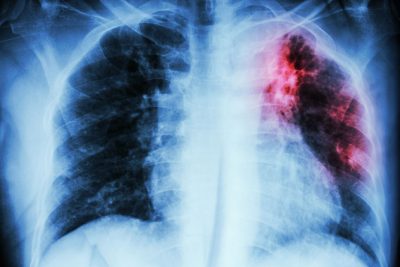

As a result, patients often wait in the hospital, hoping to be un-GOTCHed, while the PHD takes days, and sometimes weeks, to decide whether the patient is appropriate for discharge, requiring serial sputum assessments, a formal determination of the home environment, and arranging for medical assessment of any children in the home — and sometimes becoming distracted by other issues (e.g., whether that back pain described in a physician progress note on Tuesday [from spending too much time in bed] requires a computed tomography scan of the lumbar spine just in case they have spinal TB). Minimum requirements for de-isolation in the United States generally include two weeks of effective treatment and three consecutive negative daily smears. Thus, two recent patients with severe cavitary disease spent four months in isolation in our hospital, both becoming severely depressed to the point of incapacity, while they waited for negative smears. And a recent patient with extra-pulmonary nodal disease was kept in isolation in the hospital for five days of effective therapy despite three negative sputum smears and negative TB PCRs — just in case.

I once spent a week arguing with the then-TB official while a young woman with an abnormal chest X-ray was stuck in the hospital in isolation, unable to produce sputum for testing with repeated attempts at induction. The TB official insisted a bronchoscopy be performed to “prove” she was smear negative, which the patient declined. When has the absence of sputum not been an adequate marker of lack of infectivity?